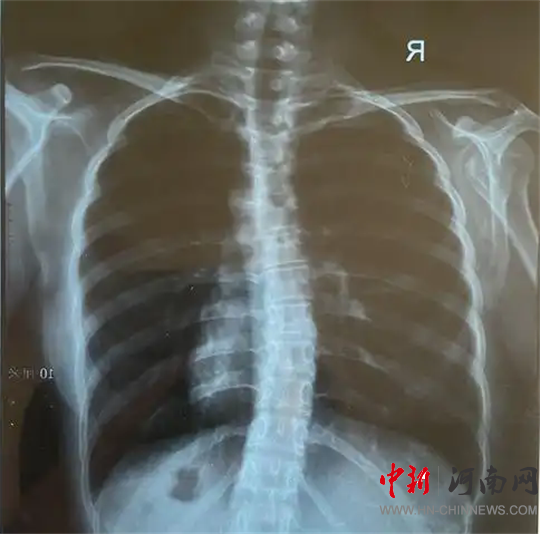

檢查結(jié)果為

脊柱側(cè)彎!

脊柱側(cè)彎,又稱脊柱側(cè)凸,是指脊柱偏離正中位置,身體向一側(cè)彎曲的骨骼畸形。

脊柱側(cè)彎絕大部分發(fā)生在青少年時(shí)期,是嚴(yán)重危及青少年群體身心健康的常見疾病,具有發(fā)病率高、起病隱匿等特點(diǎn),發(fā)病高峰集中在10-14歲。